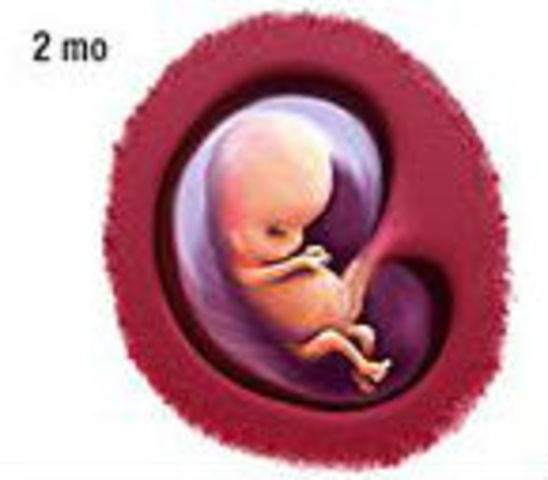

Looking for captivating what does a 2 month old fetus look like images? All, in collaboration with felix.edu.vn, presents a curated selection. Dive into the details for more.

what does a 2 month old fetus look like

We hope you enjoyed this article about what does a 2 month old fetus look like on felix.edu.vn. Let us know what you think in the comments, and discover more related content below.